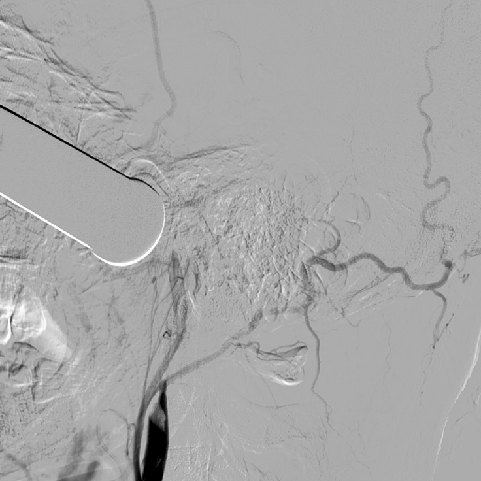

介入手术:(缺Fagarty /Merci/ Penumbra球囊导管、带膜支架)颈内动脉颅内外段置球囊保护,拔异物。